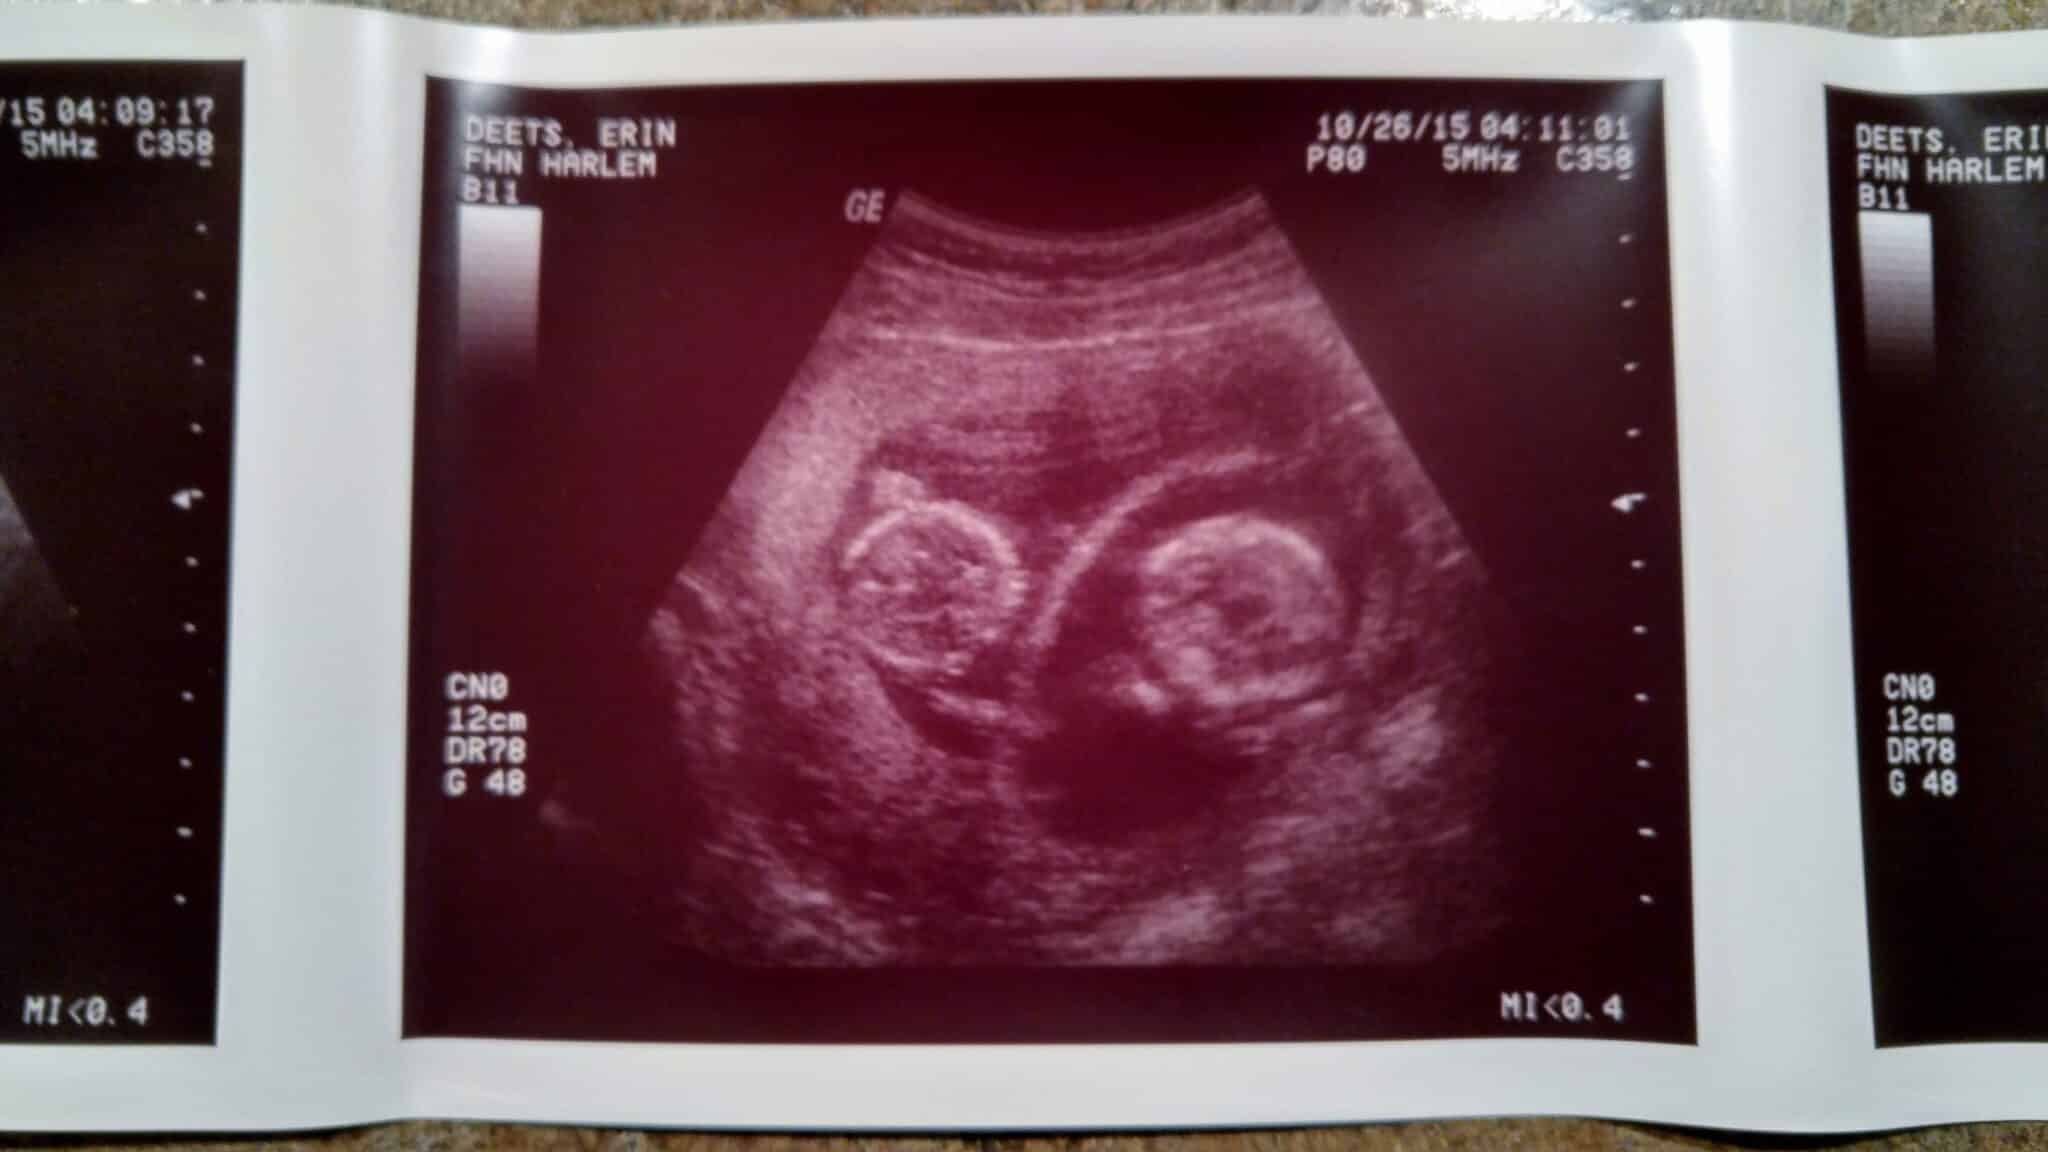

Ultrasound Photos at 12 Weeks Pregnant With Twins